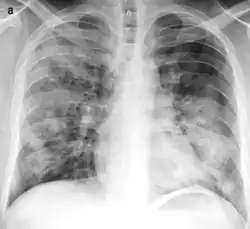

| Typical distribution of lobar pneumonia (left in image) and bronchopneumonia (right in image) | |